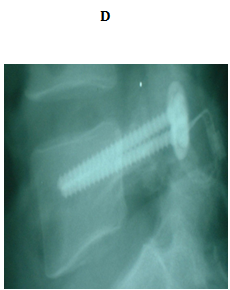

No implant failure was detected in the follow up radiographs. At the final follow up, radiological healing could be achieved bilaterally in all patients (86.6%) but four. Three of them had initial defects >3mm and one from 2-3mm, all at L5. For the healed cases, the mean time to union was 4.7 months. In the cases which did not heal, only 1 complained of significant back pain at final follow up. The other 3 did not complain of pain at final follow up (Figures 3 & 4).

Figure 3 18 years old male with bilateral pars defect at L5 underwent the procedure. (A) Preoperative lateral plain radiograph showing the defect (B) Preoperative MRI shows intact intervening disc (C, D) Immediately postoperative plain radiographs (E) CT 1 month later. Note the bone graft incorporating at the defect site.